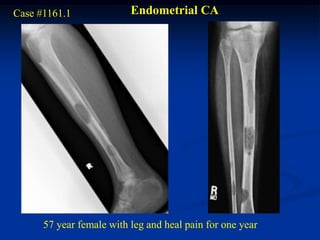

Case #1161.1              Endometrial CA

57 year female with leg and heal pain for one year

Post op cemented IM nail